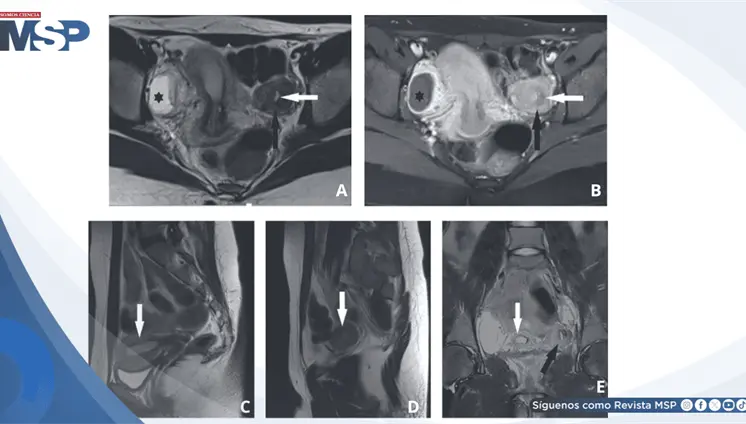

Lo que comenzó como un cuadro frecuente de dolor pélvico y dismenorrea en una mujer, terminó siendo un carcinoma folicular originado en estruma ovárico maligno. La paciente tenía solo 35 años, marcadores tumorales completamente normales y ninguna alteración tiroidea.